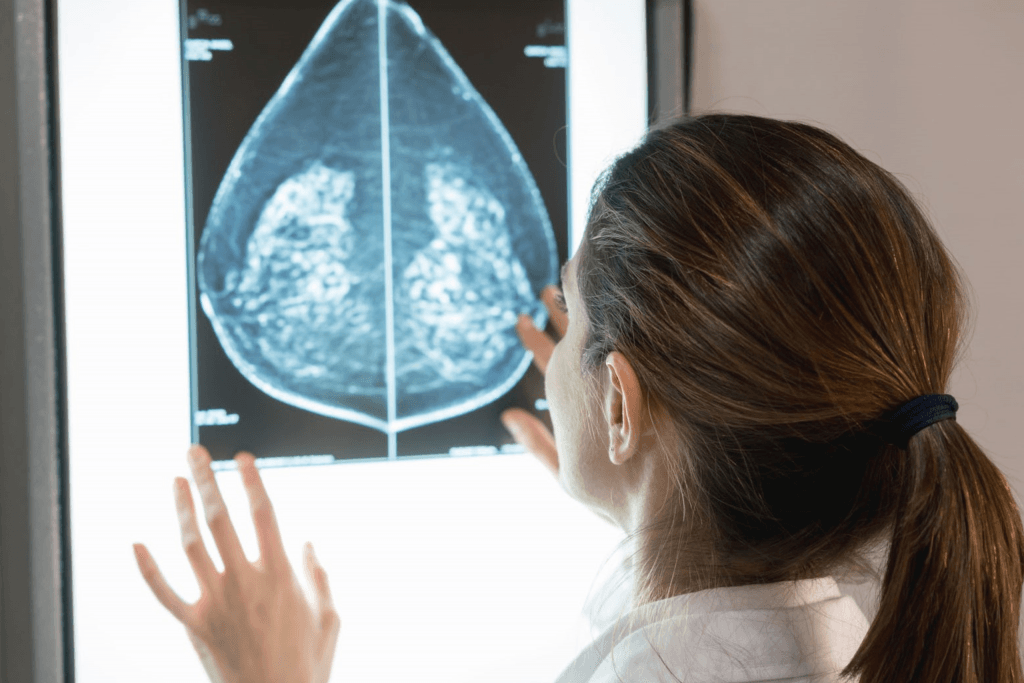

A mammogram is a specialised X-ray that helps detect breast cancer and other abnormalities—often before symptoms appear. It remains one of the most effective tools for early detection, improving the chances of successful treatment.

A mammogram uses low-dose X-rays to capture detailed images of the breast tissue. It is commonly used as a screening tool to detect breast cancer and can also be used to investigate any unusual changes in the breast, such as lumps, pain, or nipple discharge. Mammograms are highly effective at identifying small growths or changes that may not be felt during a physical exam, making them essential for early detection.